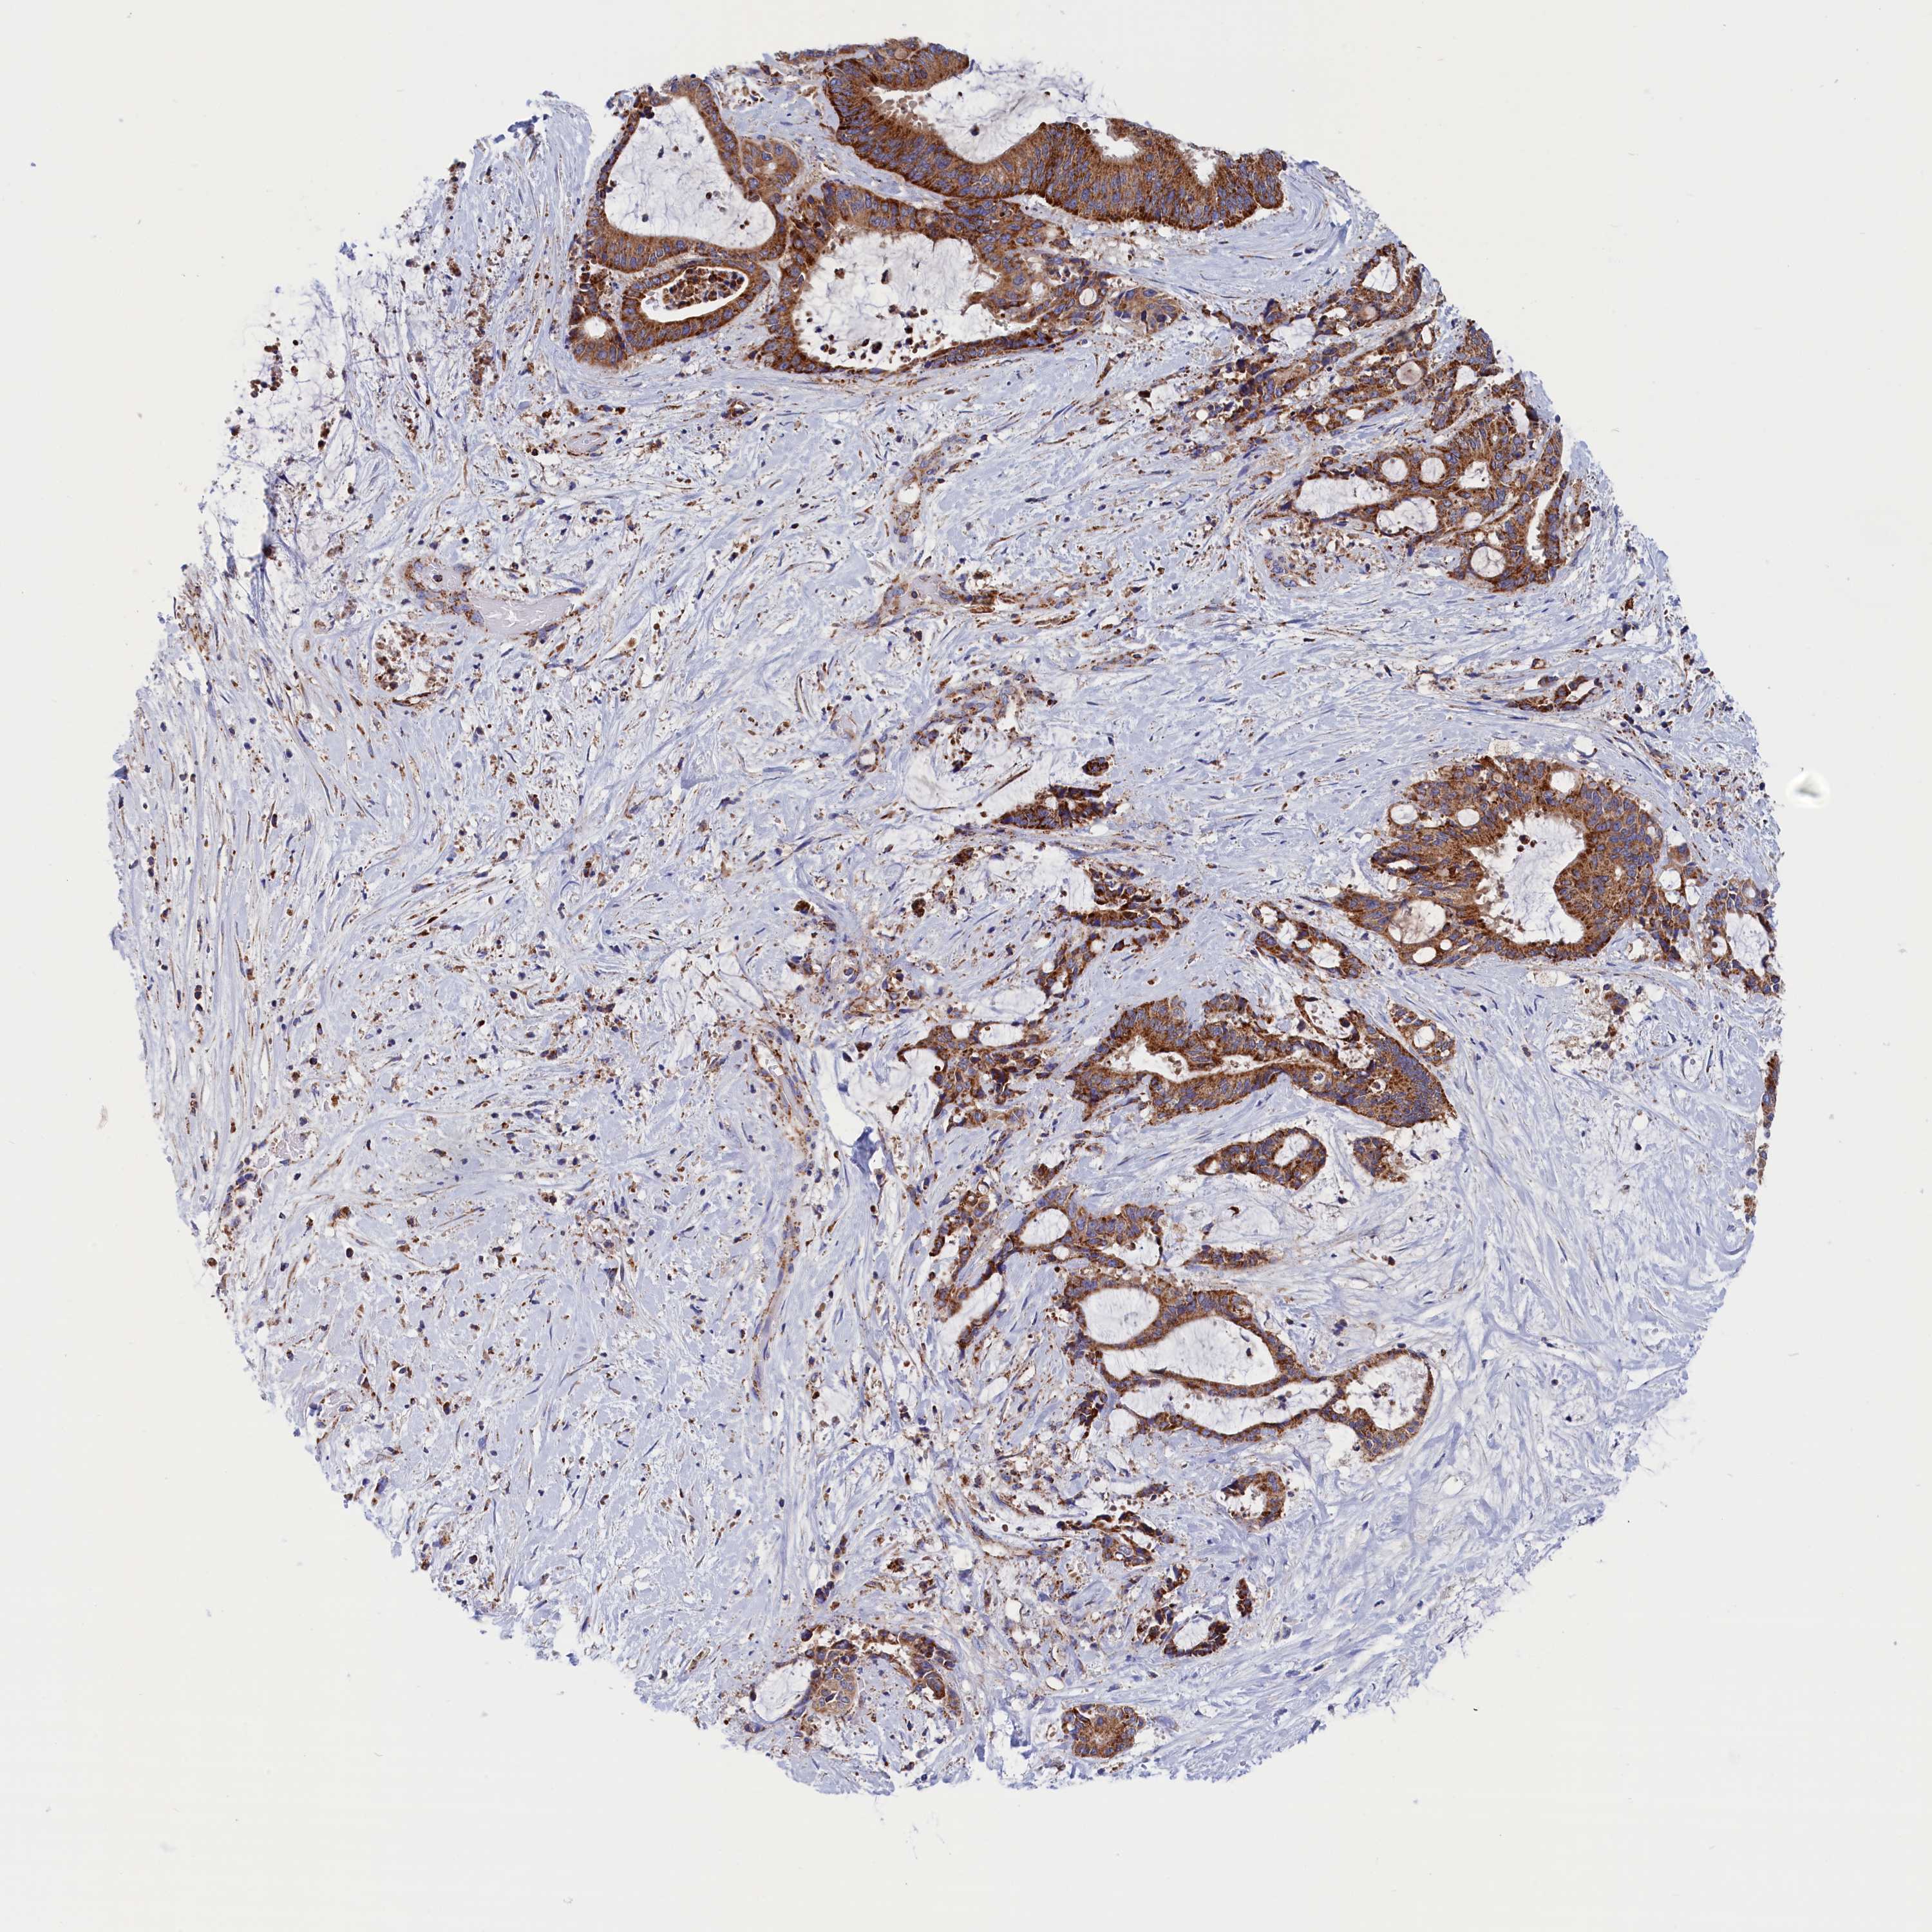

LIVER CANCER - Protein expressioni

A mouse-over function shows sample information and annotation data. Click on an image to view it in a full screen mode. Samples can be filtered based on level of antibody staining by selecting one or several of the following categories: high, medium, low and not detected. The assay and annotation is described here.

Note that samples used for immunohistochemistry by the Human Protein Atlas do not correspond to samples in the TCGA dataset.

Antibody stainingi

Antibody staining in the annotated cell types in the current human tissue is reported as not detected, low, medium, or high, based on conventional immunohistochemistry profiling in selected tissues. This score is based on the combination of the staining intensity and fraction of stained cells.

Each image is clickable and will lead to virtual microscopy that enables deeper exploration of all samples and also displays staining intensity scores, fraction scores and subcellular localization as well as patient and tissue information for each sample.

Antibody HPA042629

Antibody HPA042838

Staining

High

Medium

Low

Not detected

Intensity

Strong

Moderate

Weak

Negative

Quantity

>75%

75%-25%

<25%

None

Location

Nuclear

Cytoplasmic/membranous

Cytoplasmic/membranous,nuclear

Cholangiocarcinoma

Carcinoma, Hepatocellular, NOS